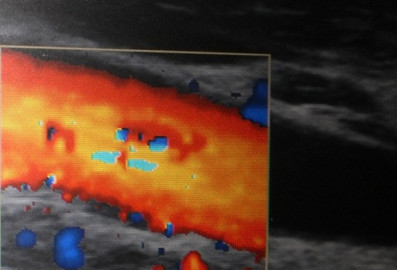

Artery with starting calcification

Sonography Ultrasound testing carotid arteries,The intima-media thickness, the wall thickness, is the main point of ultrasound measuring. The carotides com. on both sides are examined. As a precaution for heart attack, stroke and circulatory disturbance can be measured at this neck artery the wall thickness in tenths of millimeters her. Improvements of the thickened vessel walls can be documented here. Controls are carried out by 3-12 months. Contrast angiographies are meaningful to other organs, but burdensome and expensive.

Ultrasonic carotid intima- media measurements are the standard to measure of the existing Arteriosclerosis (bifurcation of Art Car.com.)

The thickness of the intima- media layer should not be about 0.08 cm (0.05 cm would be the Ideal) Also for the other arteries carotid artery is relatively good representative.

Ultrasound carotid artery

As a slight improvement in vascular calcification regressions counted by 0.1 and 0.2 mm, from 0.3 mm as a significant regression.Deterioration did not occur in the 62 patients examined.